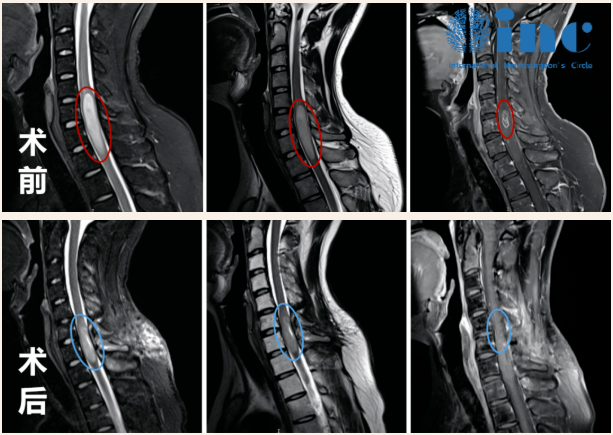

术前术后影像对比显示:脊髓内星形细胞瘤的瘤体强化部分被完整切除,肿胀效应减轻。